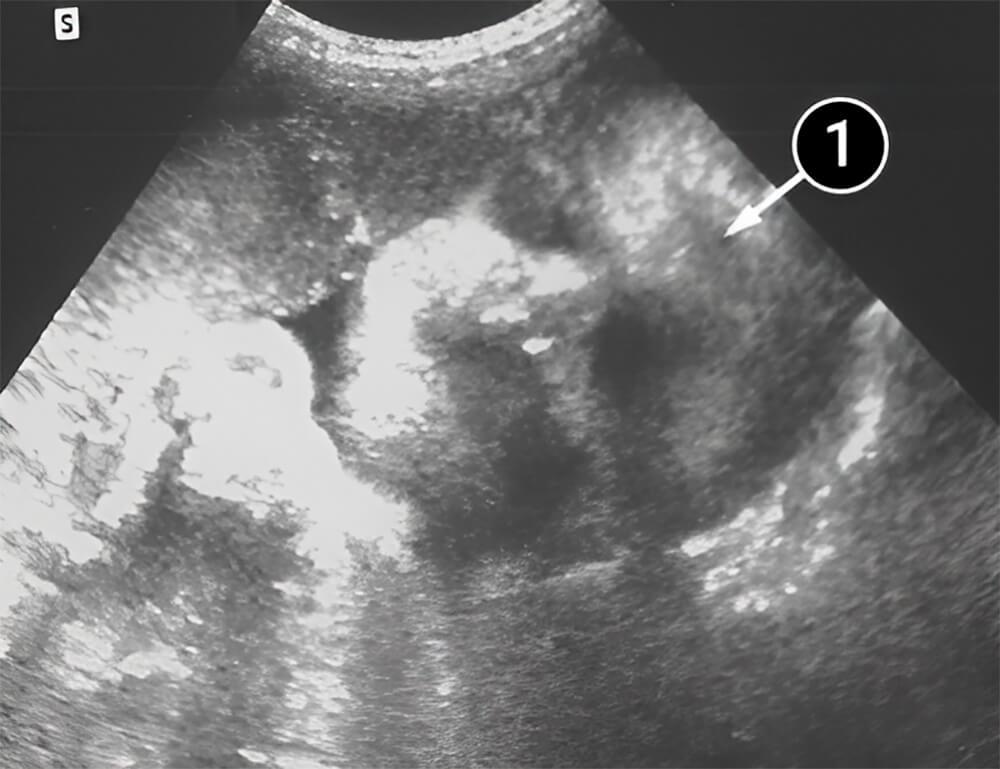

Lo que podemos ver en un ultrasonido

La imagen muestra la cabeza del bebé, así como los contornos de los ojos, la nariz y el mentón.